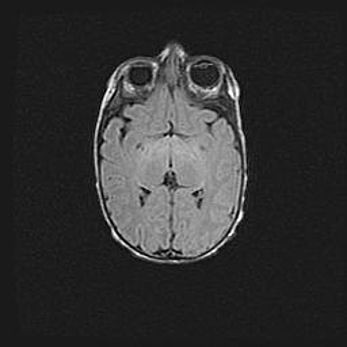

Неполная лизэнцефалия (пахигирия). Открытая гидроцефалия.

Возраст: 17 дней

Вес: 3110 г

Пол: мужской

Окружность головы: 33,5 см

Срок гестации: 35-36 недель

Лизэнцефалия—недоразвитие корковой пластинки и мозговых извилин в результате нарушения миграции нейронов коры. Поверхность мозговых полушарий гладкая. Микроскопически выявляется отсутствие нормальных слоев коры и скопление групп нейронов в подкорковом белом веществе.

Пахигирия—уменьшение числа вторичных извилин. В пораженном полушарии нервные клетки образуют толстый недифференцированный слой с неправильно расположенными нервными волокнами и группами гетеротопных клеток. Нервные клетки незрелые. Белое вещество истончено. При этом нередко аномально развит корково-спинномозговой путь.